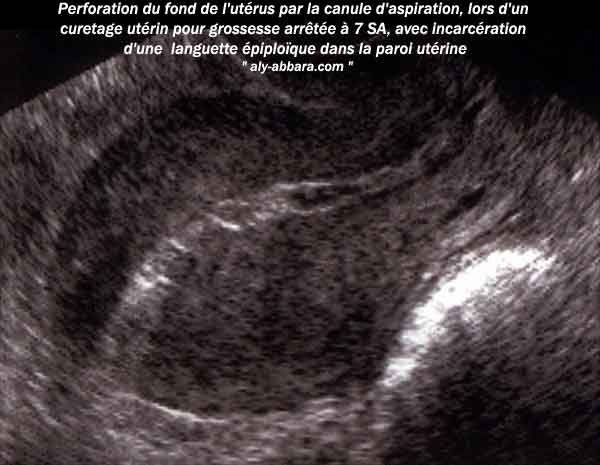

Image échographique d'une perforation utérine au niveau du fond utérin

Le diagnostic échographique était possible en raison de l'incarcération d'une languette épiploïque dans la paroi

du fond utérin (donnée cœlioscopique) ; donc la différence d'échogénicité entre le tissu musculaire (utérus)

et le tissu adipeux (épiploon) a permis de dessiner le trajet de la perforation utérine.